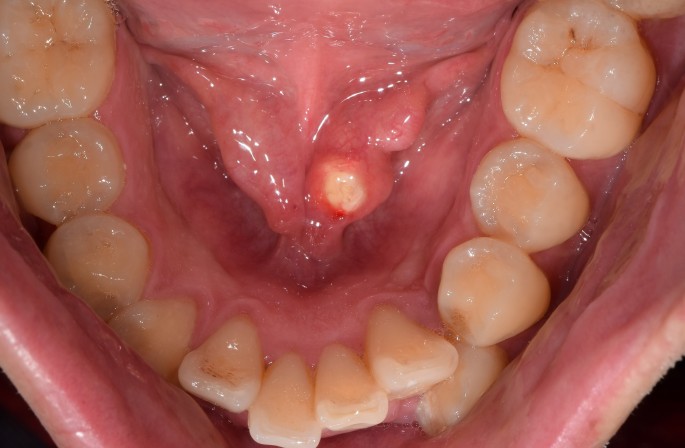

타석증(sialolithiasis), 침샘에 생기는 돌

타석증은 침샘에 돌이 생기는 질환입니다. 침샘은 입안을 촉촉하게 유지하고, 음식을 소화하는 데 필요한 침을 분비하는 기관입니다. 타석증은 침샘의 어느 부위에나 돌이 생길 수 있지만, 가장 흔하게 이하선에서 가장 잘 발생합니다. 출처 : 밥먹을 때 침샘이 부어올라요 :: 침이 배출되.. : 네이버블로그 (naver.com) 출처 : 침샘염에 좋은 음식 원인 종류 치료 타액선염 .. : 네이버블로그 (naver.com) 1. 타석증 원인 1) 침샘의 점도 증가 : 침이 끈적끈적해지면 돌이 생기기 쉽습니다. 2) 침샘의 배출 감소 : 침샘의 배출이 감소하면 침이 뭉쳐져 돌이 생기기 쉽습니다. 3) 침샘관의 염증과 칼슘염 침착 : 침샘관의 염증과 칼슘염 침착으로 인해 돌이 생길 수 있습니다. 2. 증상 1) 침..